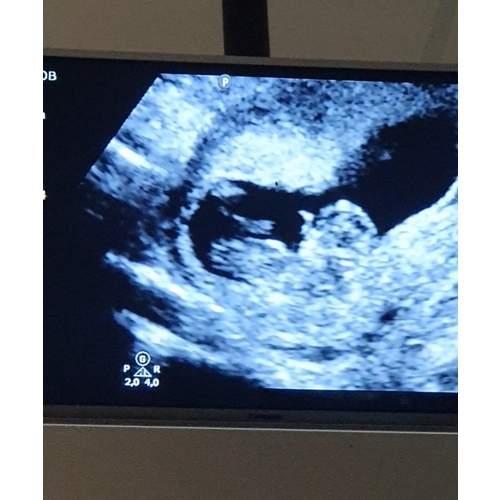

Gisteren termijn echo gehad volgens mij is dit een hele mooie nub wat denke ...

Prachtig, maar te vroeg. Met dit termijn staan 99% van de nubs nog in meisjes stand. Het kan dus alsnog veranderen en je kunt er niks over zeggen. Daarbij zoals de moderator hier aangeeft zijn er algemene topics hier voor. 馃槉